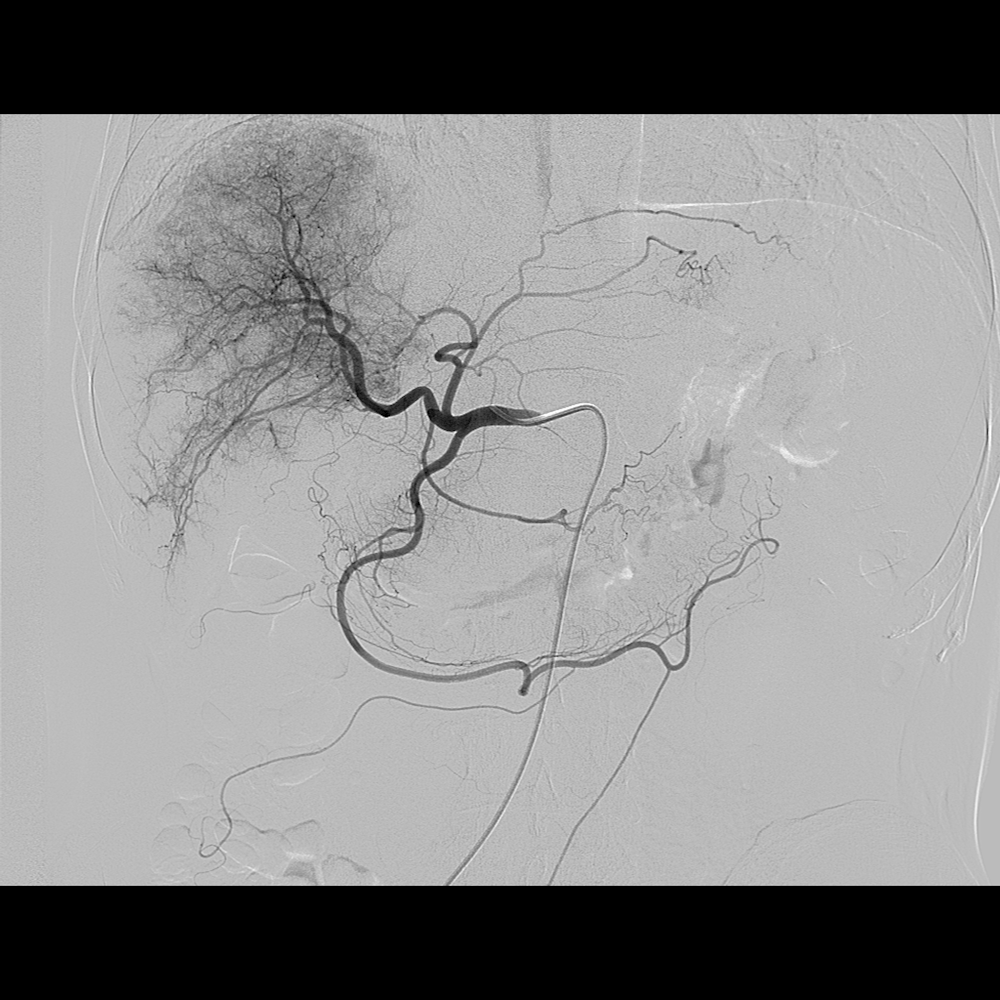

3.神经介入治疗:脑动静脉畸形、脑膜动静脉瘘、脑动脉瘤、脑动脉血栓溶解、脑膜瘤、颈动脉海绵窦瘘等微创介入治疗。

图左:病患右颈内动脉造影显示大脑中动脉有动脉瘤 右侧颈内动脉动脉瘤(红色箭头)

图右:经弹簧圈栓塞后,动脉瘤萎缩消退